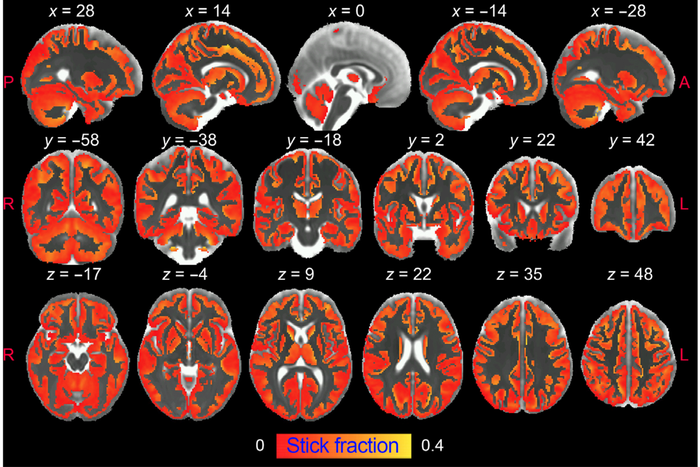

图:UMH-CSIC神经科学研究所的研究人员开发了一种创新策略,允许使用扩散加权磁共振成像(dw-MRI)对大脑灰质中的小胶质细胞和星形胶质细胞激活进行成像。

在这项研究中,来自UMH-CSIC神经科学研究所的研究人员开发了一种创新策略,允许使用扩散加权磁共振成像(dw-MRI)对大脑灰质中的小胶质细胞和星形胶质细胞激活进行成像。